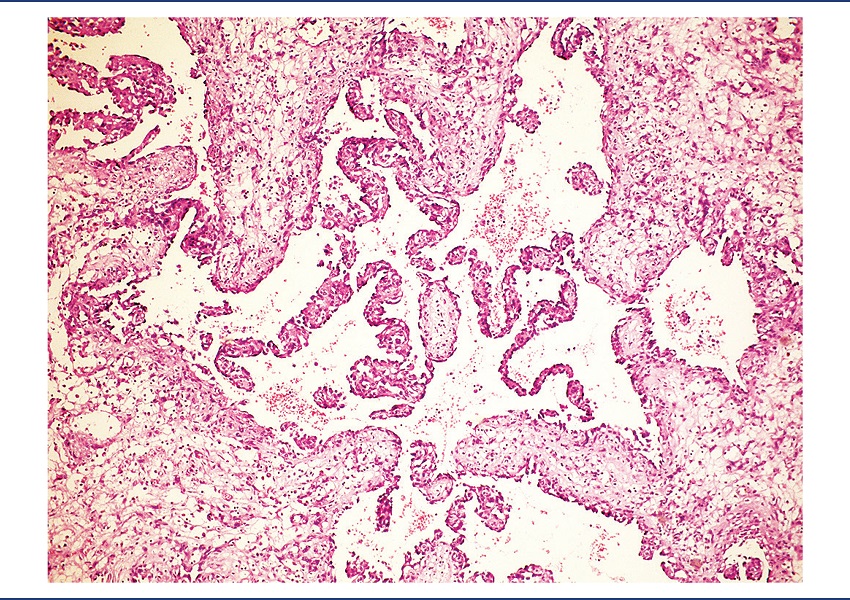

On pathological examination, the specimen was received fragmented, measuring 9.2 × 7 × 4 cm. There was a brownish nodule with hemorrhagic areas, measuring 4 cm in diameter, apparently infiltrating the cardiac wall (Figure 2). Microscopically, it was identified as a mesenchymal neoplasm, characterized by the proliferation of atypical endothelial cells with irregular nuclei, sometimes round sometimes spindle, without evident nucleolus, forming vascular spaces, papillae, and solid areas. Mitoses were frequent and necrosis was not observed. The lesion permeated cardiomyocytes, which presented clear cytoplasm and hypertrophic nucleus (Figures 3 to 7). There was infiltration of the visceral pericardium. The diagnosis was primary cardiac angiosarcoma.

HE: hematoxylin and eosin.

Histology can reveal different aspects, depending on the degree of differentiation. Well-differentiated areas are made by atypical pleomorphic endothelial cells, which form papillary structures or vascular channels. The poorly differentiated areas are formed by spindle anaplastic cells in solid pattern(7). The tumor presented both well-differentiated and poorly differentiated areas.